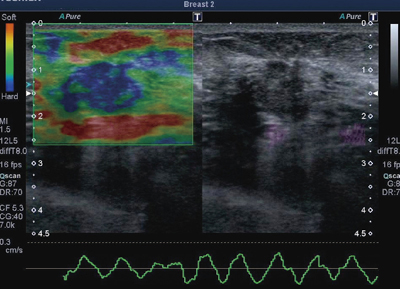

●組織の硬さを映像化する“Elastography”(図3)

プローブの圧迫動作により,病変部位の硬さ(弾性)を映像化します。腫瘍性病変と周囲組織の硬さを相対的に比較することができます。プローブの速度をビジュアル化することで圧迫の与え方が適正かどうかの確認ができ,より再現性の高い検査が可能です。

図3 Elastography